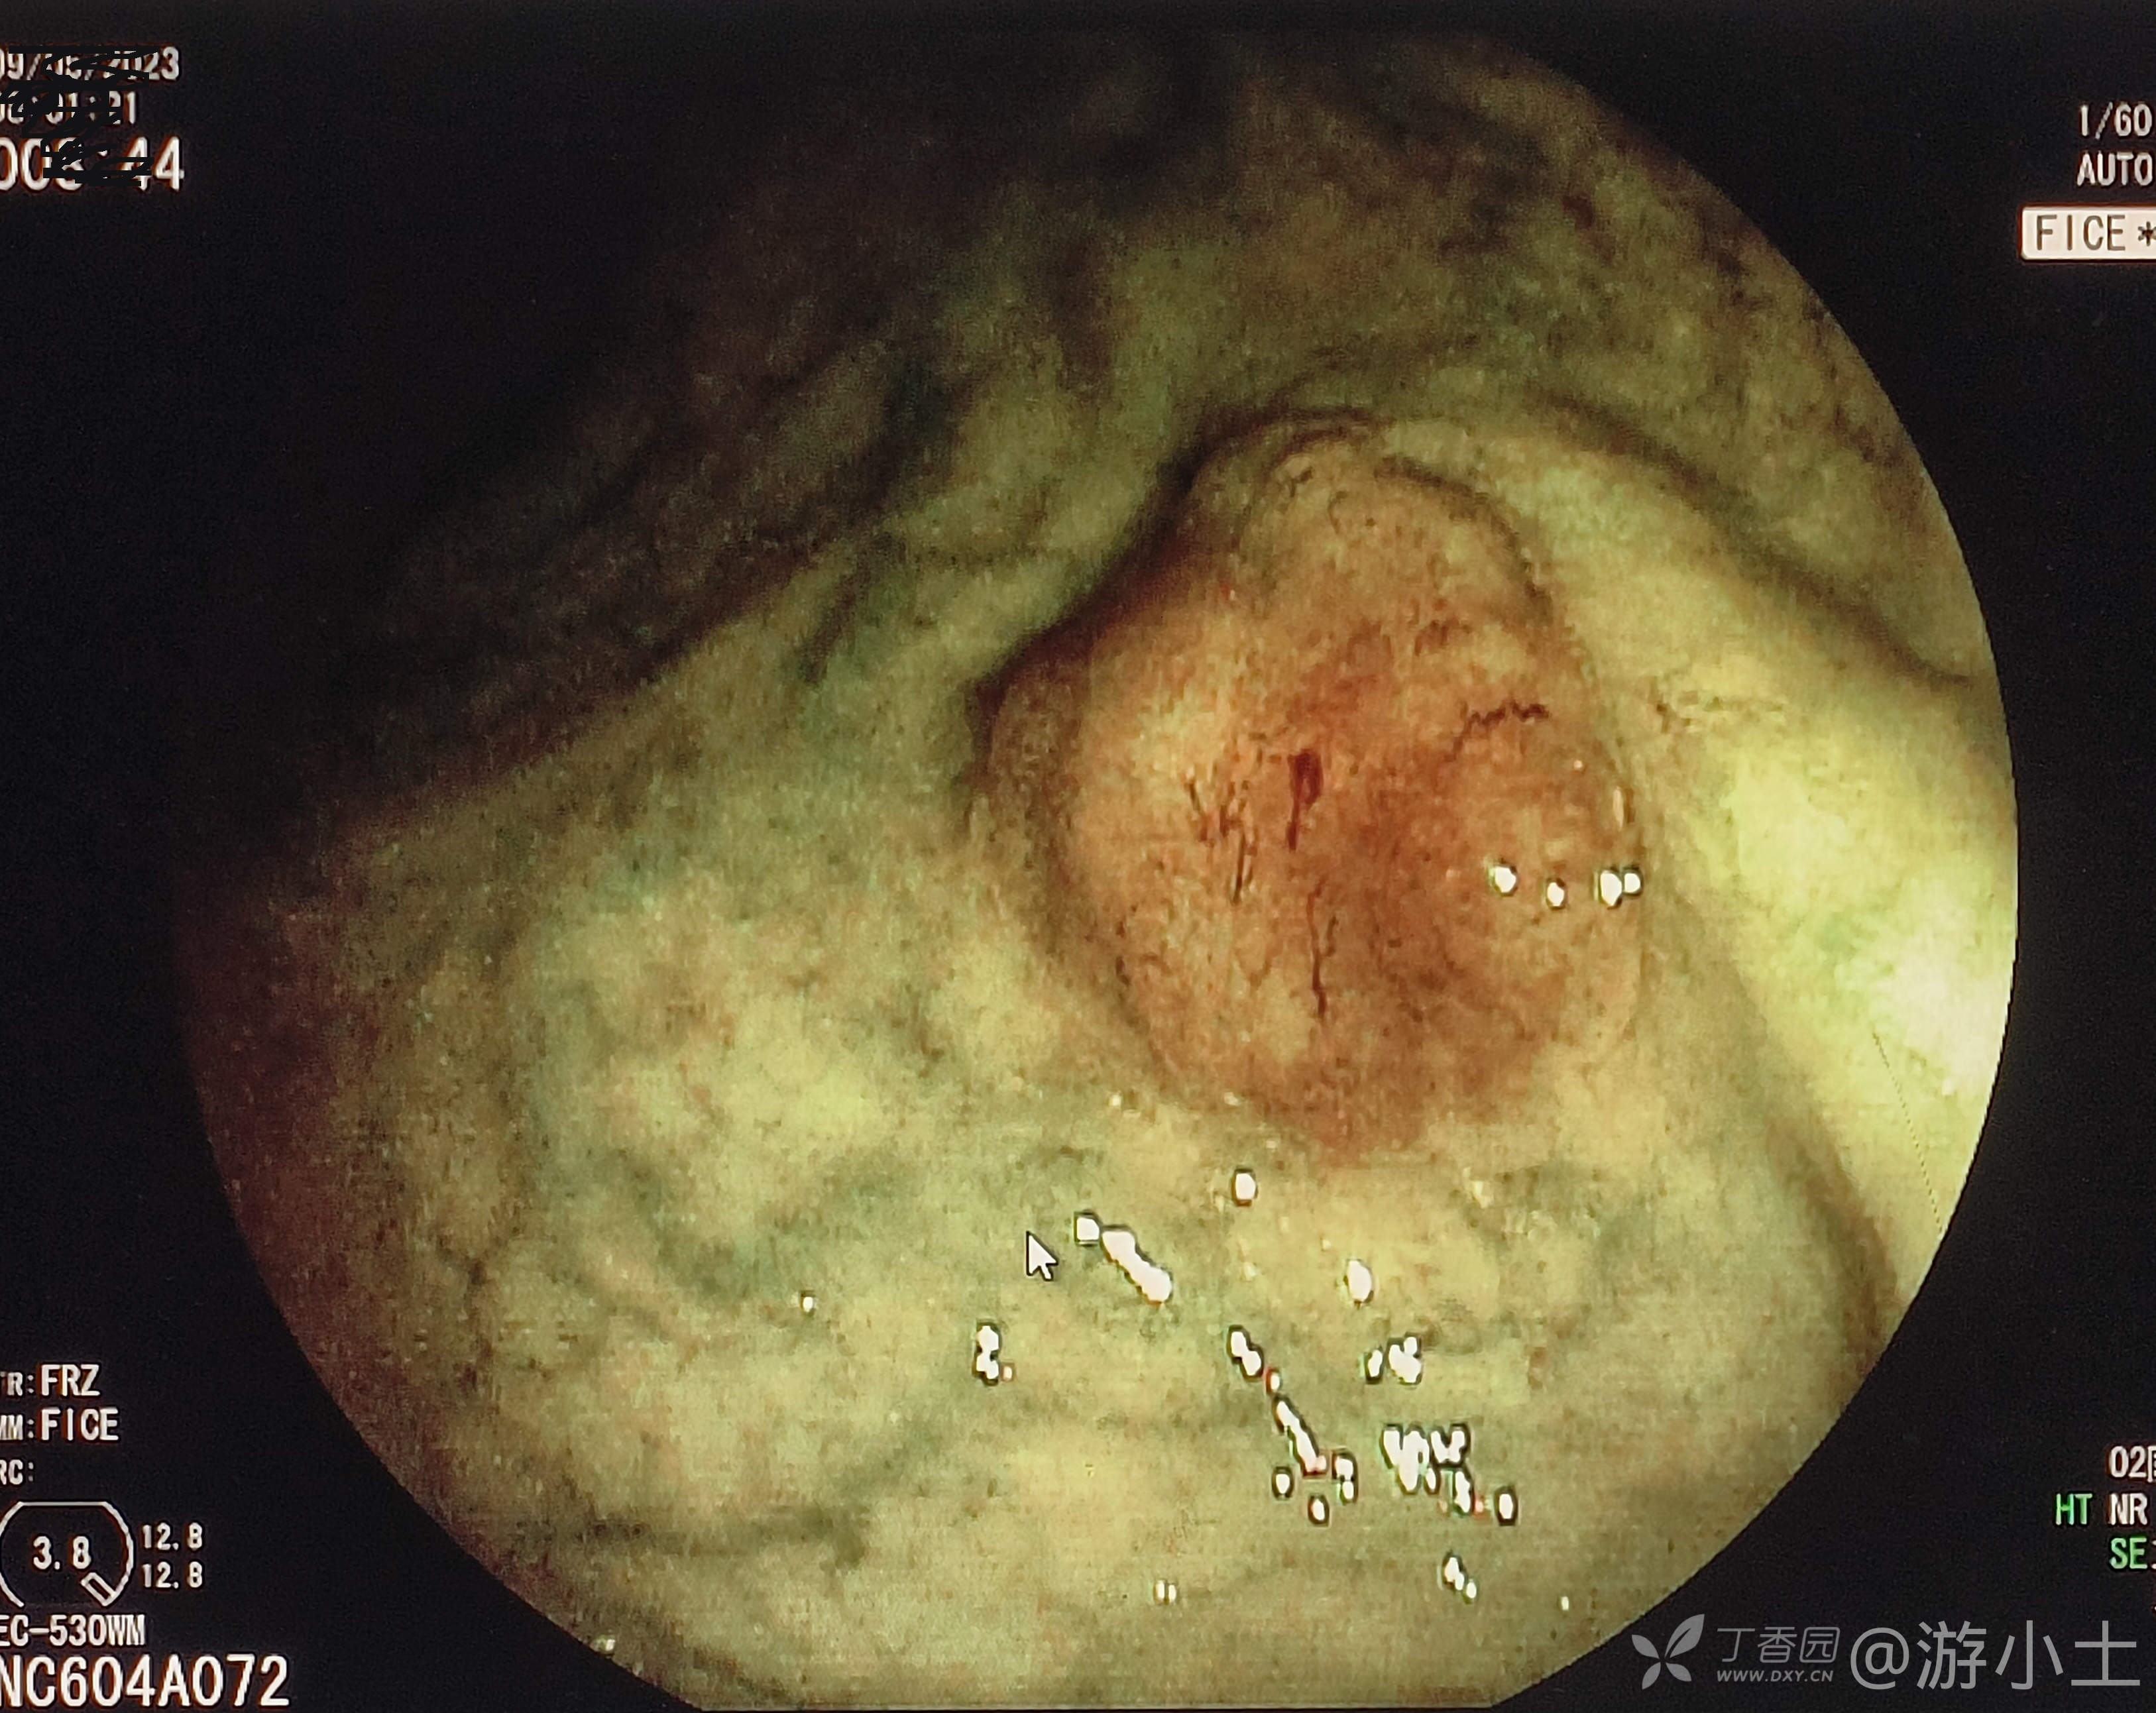

患者性别:男,74岁,既往体健,健康查体发现直肠正常如此一例病灶。

讨论:猜猜病理到底是什么样?

直肠腺癌 (14)